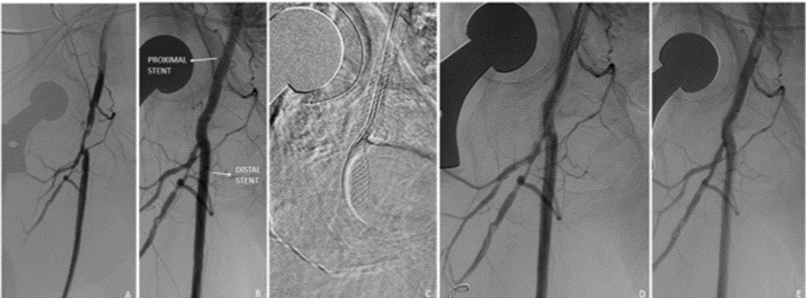

图3. 单支架,拘禁股深动脉。59岁女性急性CLI。初始造影:股总动脉和股深动脉主干明显狭窄(A)。股总动脉6mm球囊扩张,并植入6mm×40mm SUPERA支架(B)。随后,导丝进一步进入SUPERA支架,并在股深动脉使用3mm×60mm球囊扩张(C,D),显影良好(E)

图片